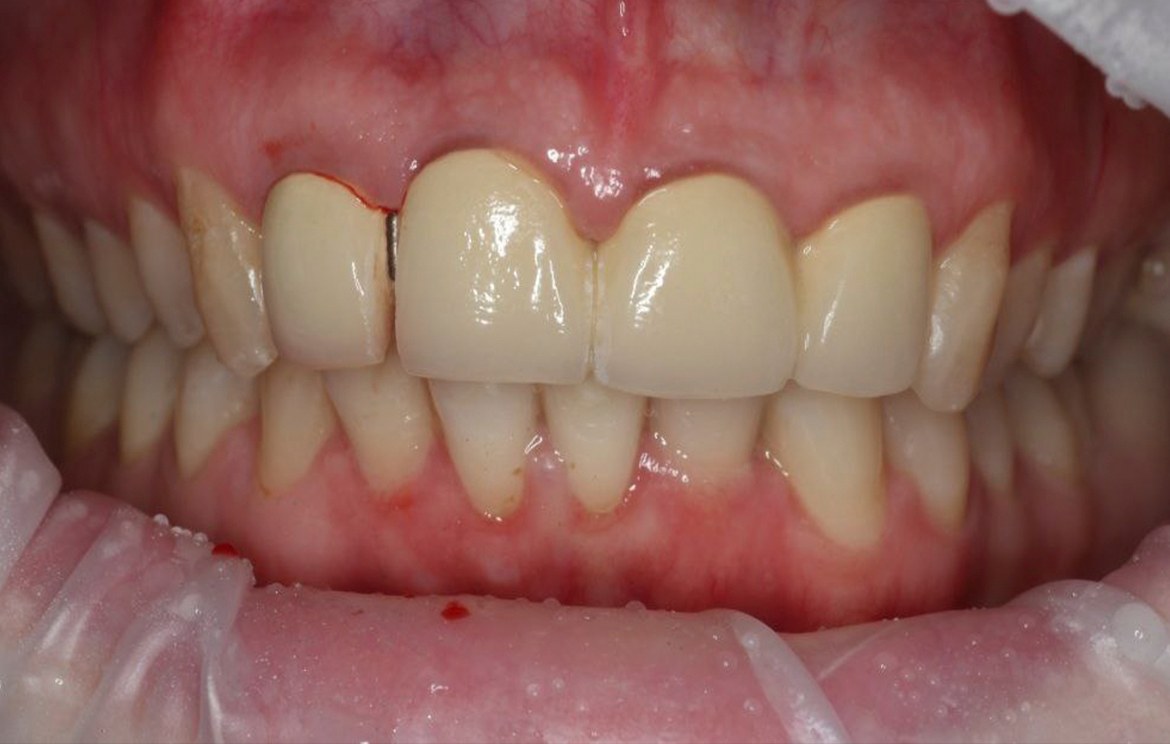

Наши работы